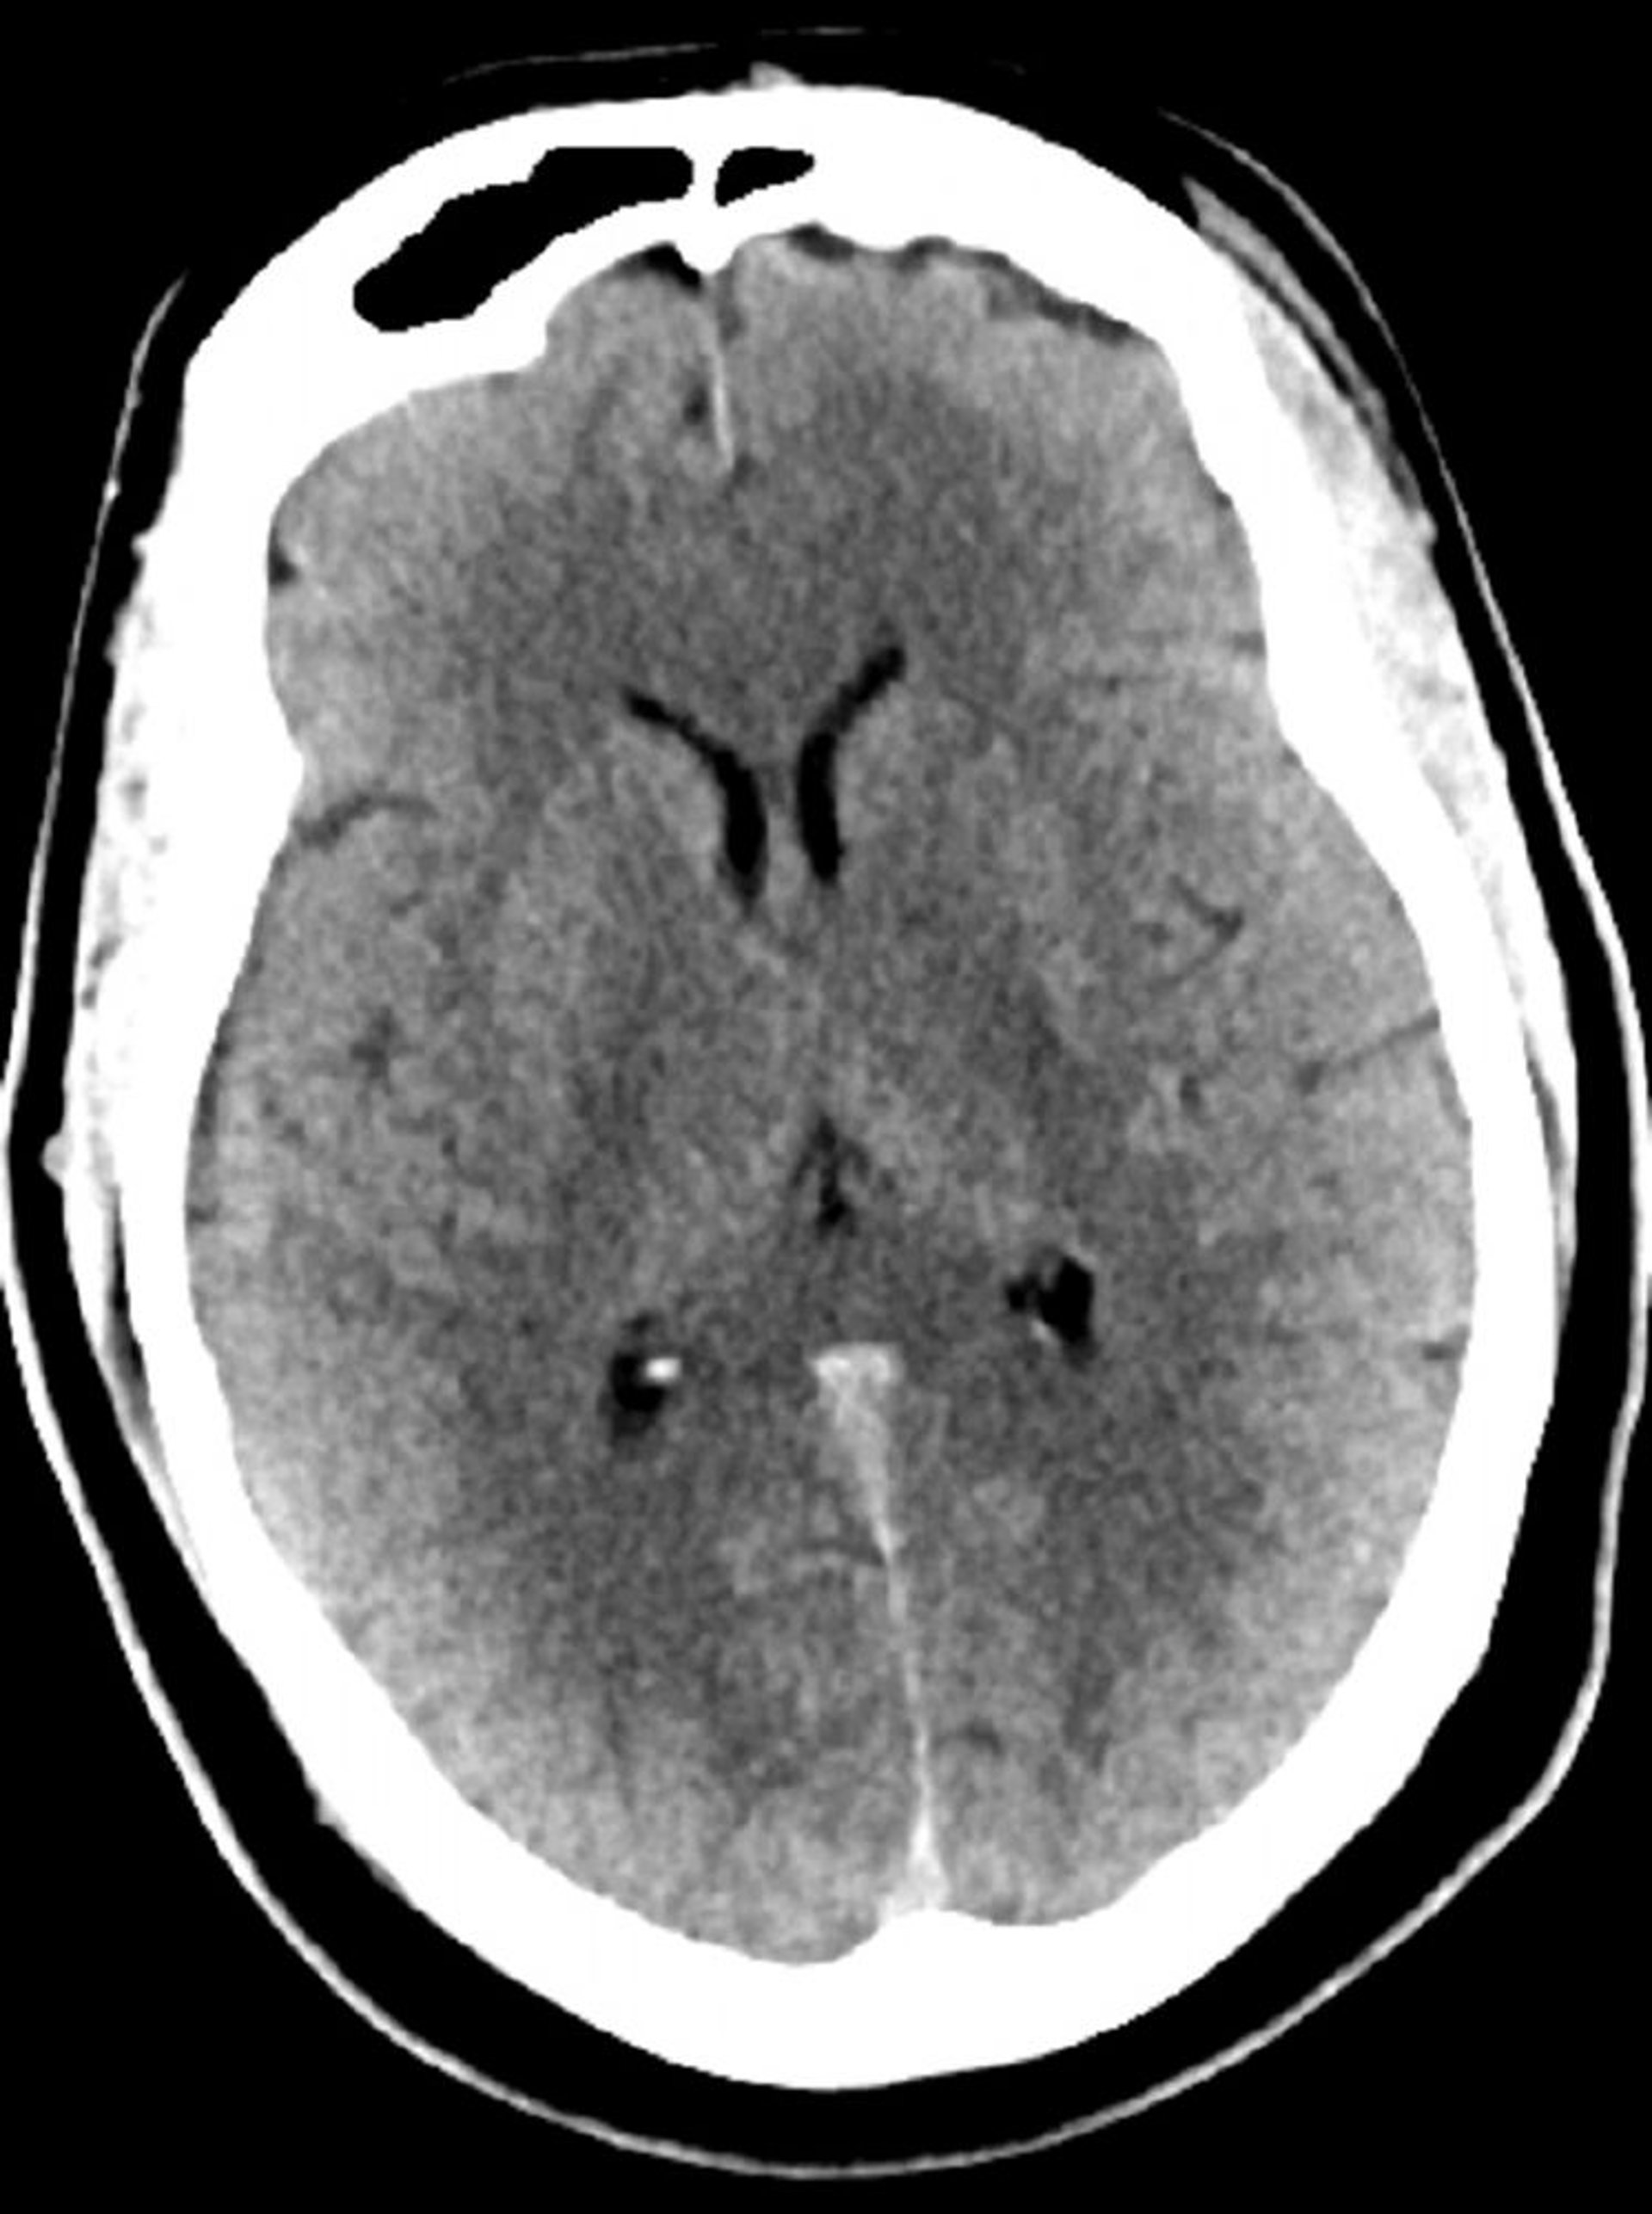

Стандартное КТ-сканирование головы (взрослые, возраст 30 лет) – слайд 5

Это изображение – обычный КТ-снимок головы взрослого человека в возрасте 30 лет. Ни внутри паренхимы мозга, ни вне ее не наблюдается накопления жидкости или кровоизлияния. Дифференцировка серого и белого вещества сохраняется. Размер желудочков и характеристики борозд в норме.